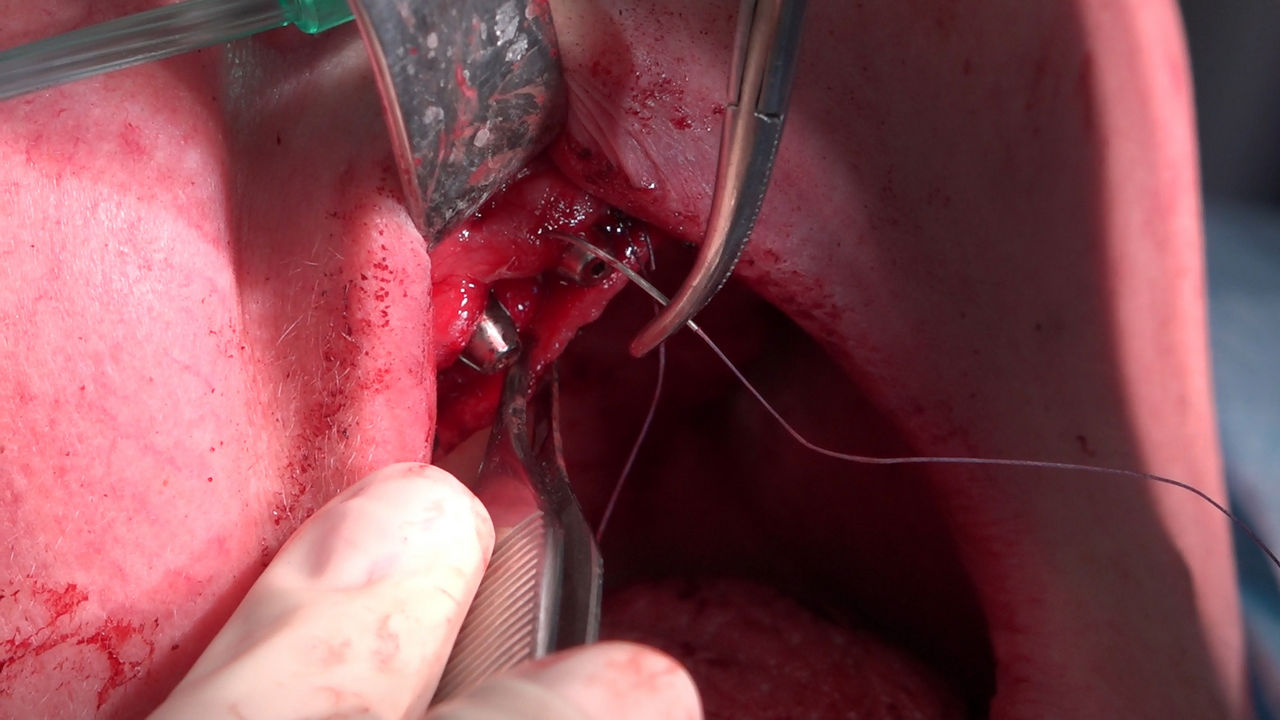

Practiculum Implantologii to szkolenie dla adeptów implantologii zorientowane na praktyczne opanowanie procedur zabiegowych i wprowadzenie implantologii do własnej praktyki. Dla Kursantów Grupy A, X Sezonu, 9 Sesja stanowiła ostateczny sprawdzian umiejętności zabiegowych zdobytych podczas procedur wykonywanych w trakcie szkolenia pod kierunkiem dr n.med. Violetty Szycik i dr Małgorzaty Piotrowskiej. Zobacz więcej na: www.practiculum.pl